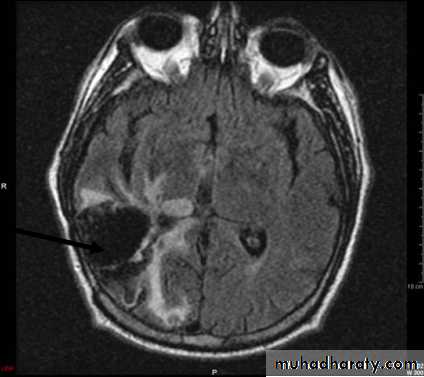

• Peritumoral edema

• Necrotic centerBenign

• Computed Tomography scan (CT scan) with/without contrast• Magnetic Resonance Imaging (MRI) with/without contrast